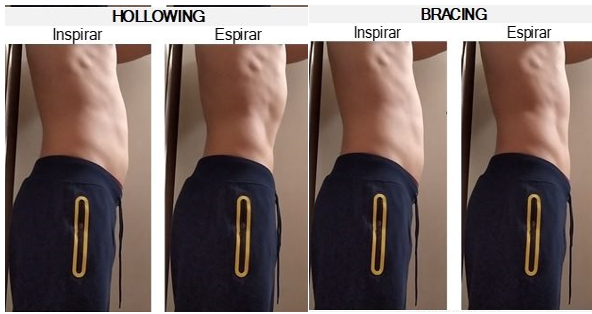

Abdominal Hollowing이 척추를 안정시키는 것을 보였습니까?

아직 의견의 논쟁이 있지만 크레이그 리벤슨선생님의 이 칼럼에서는 Abdominal Hollowing

은 척추의 안정화 운동시에는 보이지 않는 반면, abdominal bracing은 보여진다라고

언급하고있습니다.

이와 연관하여 2009년도에 나온 크레이그 리벤슨 선생님의 논문에서는

Abdominal bracing은 능동적인 다리 거상 레그레이즈를(Active Straight Leg Raise Test of

Mens (Liebenson et al.2009) 하는 동안 허리의 축회전강직 (Axial Rotation Stiffness)통한

척추의 견고함을 증가시키고 Active Straight Leg Raise test동안에 척추의 불안정성을

만들수있는 축회전(Axial Rotation)을 감소시킬수 있다라고 언급하였습니다.

(Liebenson et al., 2009)

2020년도 연구논문에서는 다리의 무릎을 펴고 신전하는 Active Leg Raise(SLR)동작과

무릎을 구부리고 다리를 거상시키는 Bent Knee Fall out(KFO)동작수행시

Abdominal Hollowing과 Abdominal Bracing 그리고 휴식시를 비교한 논문연구를

언급해보려고합니다.

이 연구에서는 Abdominal Bracing방법이 Abdominal Hollowing방법보다 다리

신전거상(SLR)동작 수행시에 골반의 회전각도가 더 줄어들었다고 언급하고 있습니다.

물론 크레이그리벤슨선생님의 이 칼럼과 앞선 논문에서의 연구결과 에서처럼

Abdominal Bracing의 방법이 골반회전감소와 축강성(Axial Stiffnes)에 도움이 더 되고

Abdominal Hollowing방법은 그 효과가 적을수 있습니다.